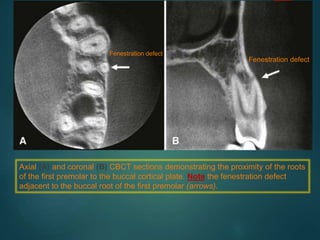

Axial (A) and coronal (B) CBCT sections demonstrating the proximity of the roots

of the first premolar to the buccal cortical plate. Note the fenestration defect

adjacent to the buccal root of the first premolar (arrows).

Fenestration defect